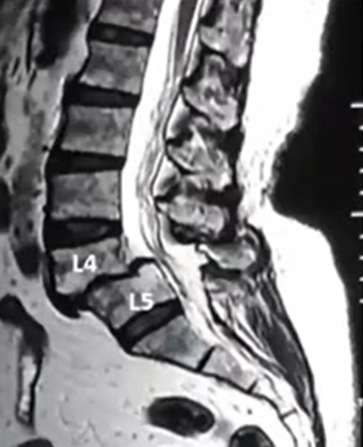

Spinal fusion is a surgical procedure that permanently joins two or more bones of the spine so they heal into one solid bone. This eliminates painful movement between them and stabilizes the spine.

- Patients with slipped discs that keep recurring

- Severe back pain due to spinal instability or arthritis